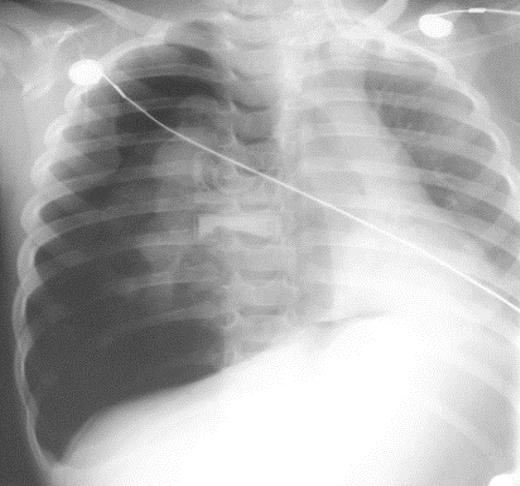

Figura 9. Hemotórax por acumulo de sangre en espacio pleural por laceración pulmonar Figura 10. Hemotórax → aumento de radiopacidad en hemitórax izquierdo Figura 11. La radiografía de tórax en posición vertical muestra una combinación de hemoneumotórax (flechas gruesas y delgadas, respectivamente). Figura 12. TAC tórax → ↑sensibilidad y especificidad para diagnóstico de hemotórax como se muestra en la imagen en lado izquierdo